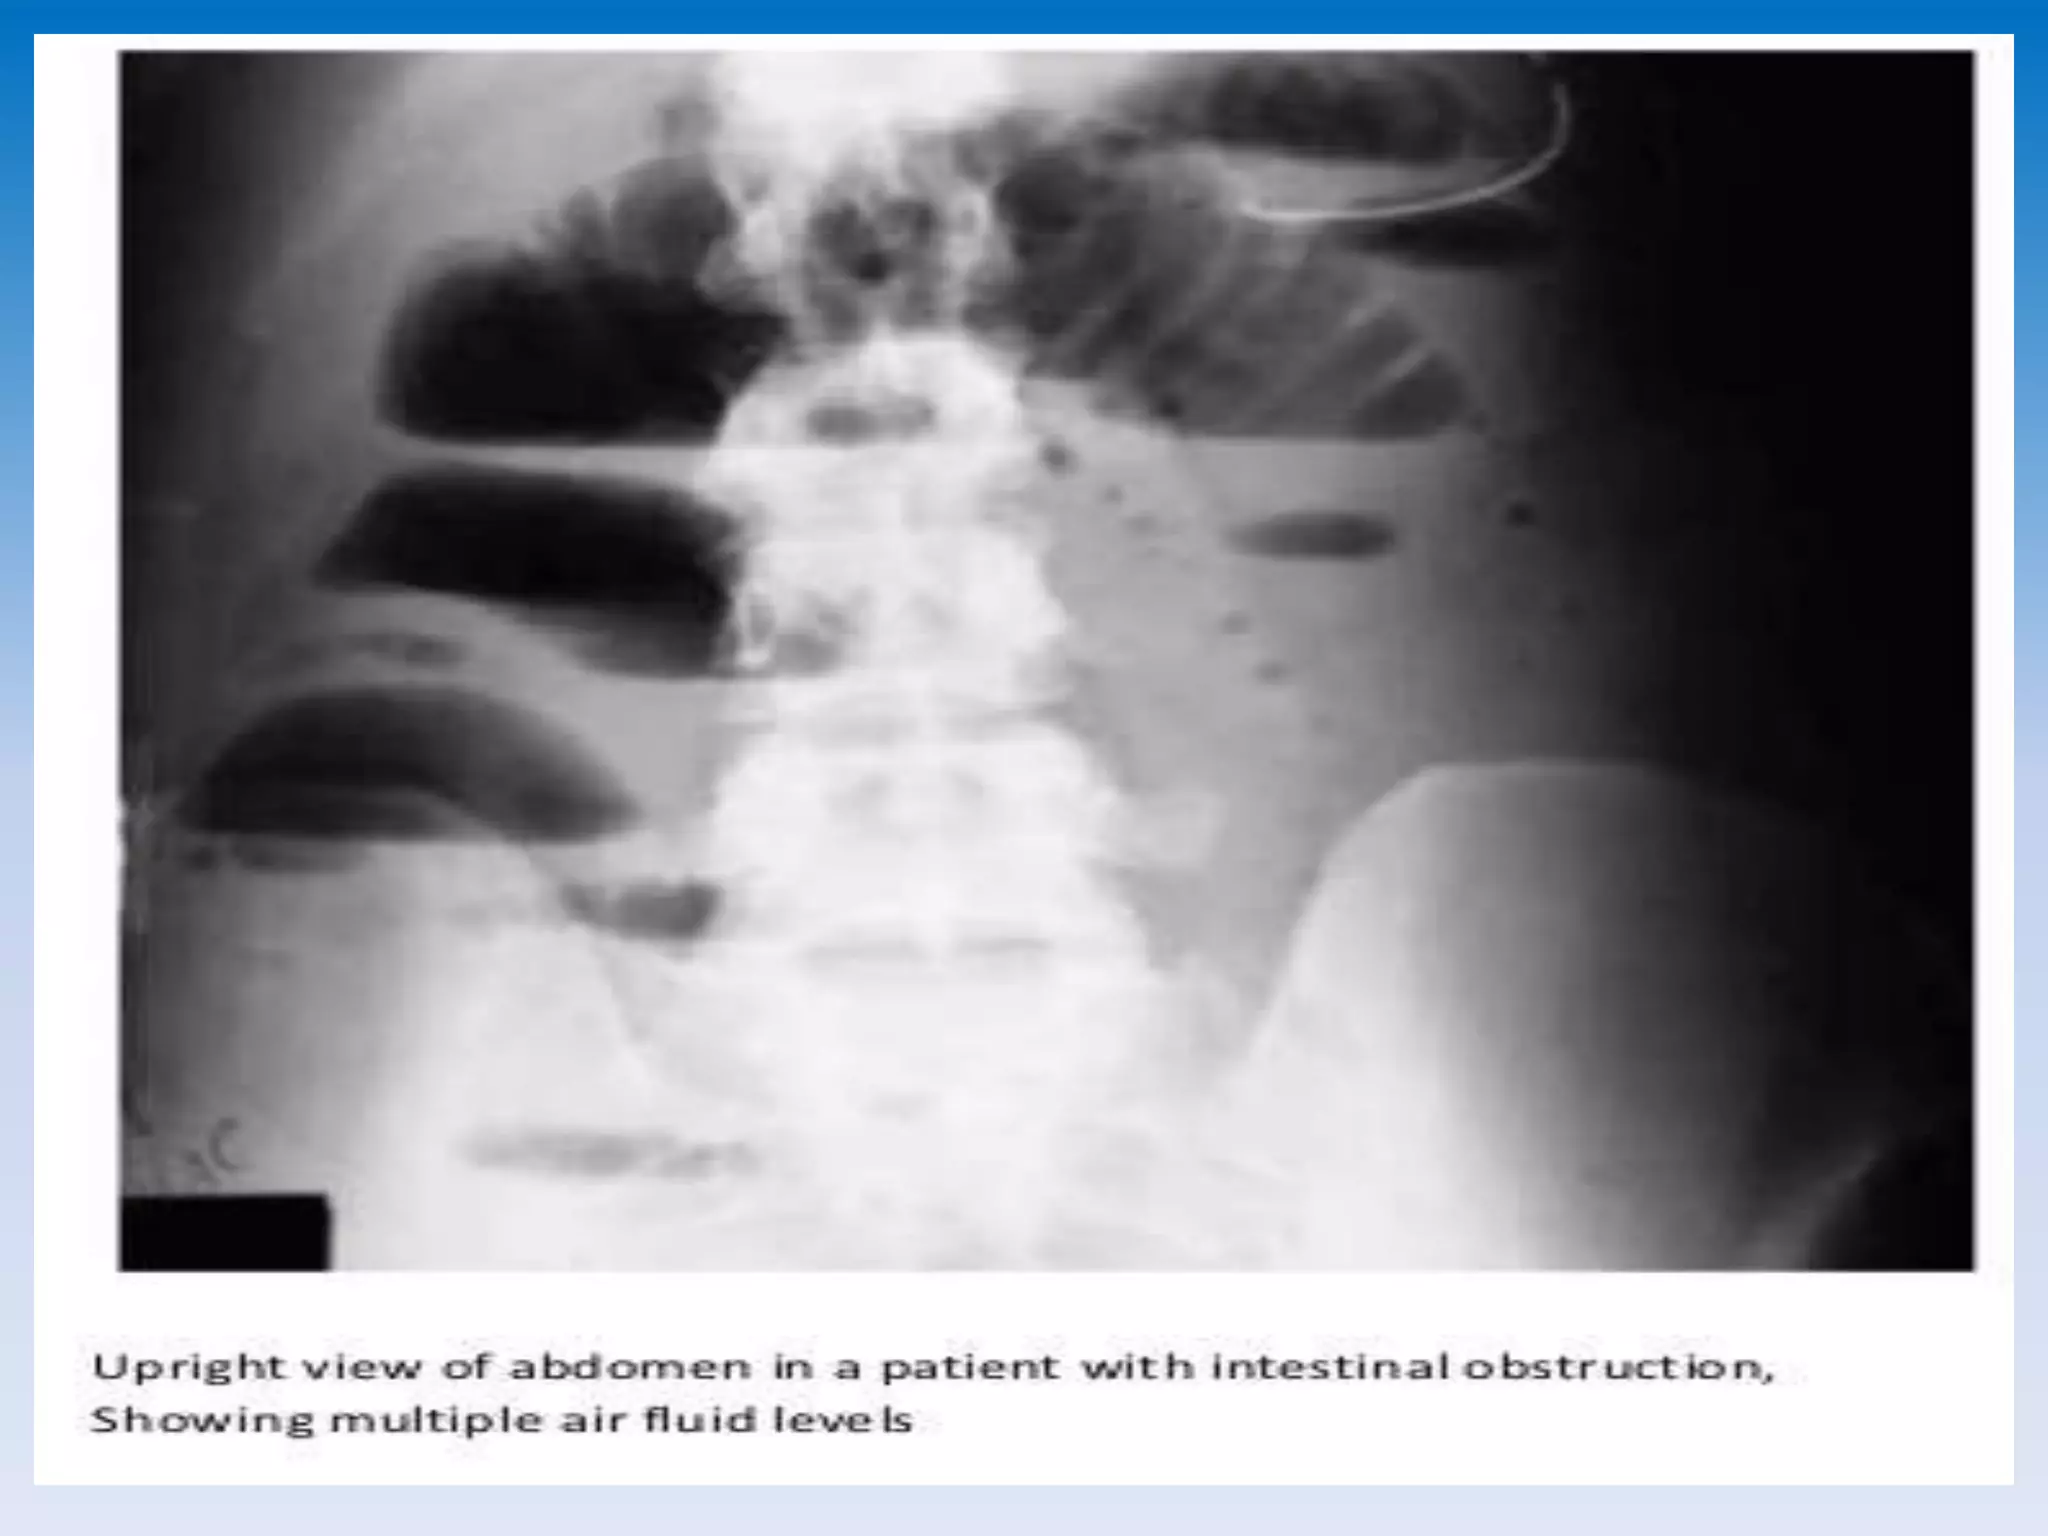

This document discusses radiological imaging techniques for diagnosing different types of intestinal obstructions. It mentions small bowel obstruction and provides information on sigmoid volvulus. The document is written by Dr. ABD ALLAH NAZEER and analyzes imaging of various intestinal blockages and conditions.